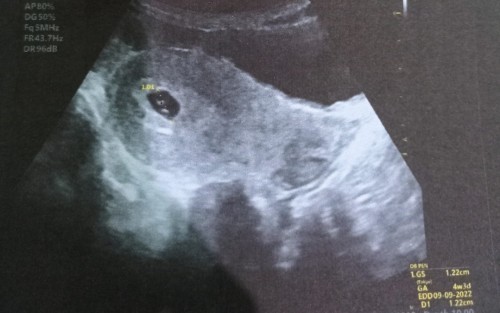

Telat mens sampai 17 hari, terakhir testpack hari ke-10 dan hasil negatif. Sampai sekarang mau tes lagi masih takut. Yang sy rasakan sekarang adalah di perut bagian bawah kiri seperti mengganjal, sering pusing, gampang cape, kalo malem mesti mual², kalo di pagi hari rasanya kaya mau pms, sering banget keluar cairan putih. Menurut bunda kira² jadi ga ya? Karna jujur, Ini sebenarnya bukan yg diharapkan karna bocil barusan berumur 2tahun3bulan. Kalo ditanya pake kb apa ga, suami yg pake kb manual 😅, dan di bulan November suami bener² ga beli. Jadi kita mentahan aja. Dan akhirnya, hmmmm kok telat 🤣 #seriusnanya #bantusharing #ingintahu #pleasehelp #pejuang_garisDua